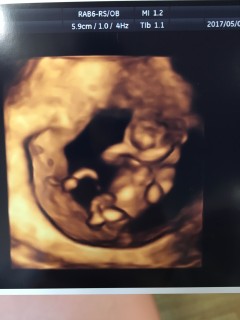

割と鮮明な4Dで撮ってもらいました。5.9ミリだそう。 全く実感がなかったのに、こんな小さいのに一人前に人間で感動しました! 指しゃぶりをしたり途中から寝たりしてました。笑